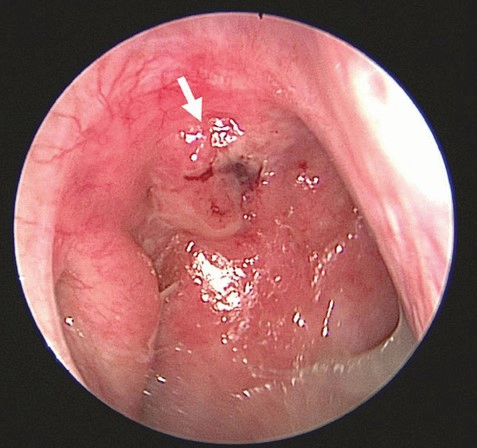

비인두암은 비인두라고 불리는 부위, 즉 코와 입 사이의 공간에 발생하는 암입니다. 이 암은 흔하지 않지만 발생하면 다양한 증상을 보이며 치료가 필요합니다.

비인두암 환자들은 코에서 무작위로 출혈이 발생할 수 있으며, 이는 종종 비인두암의 초기 증상 중 하나로 나타납니다.